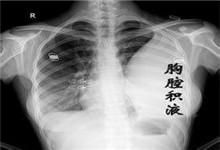

惡性胸腔積液CT圖在體格檢查時可發現患側呼吸運動減弱,肋間隙飽滿,氣管向健側移位,積液區叩診為濁音,呼吸音消失。